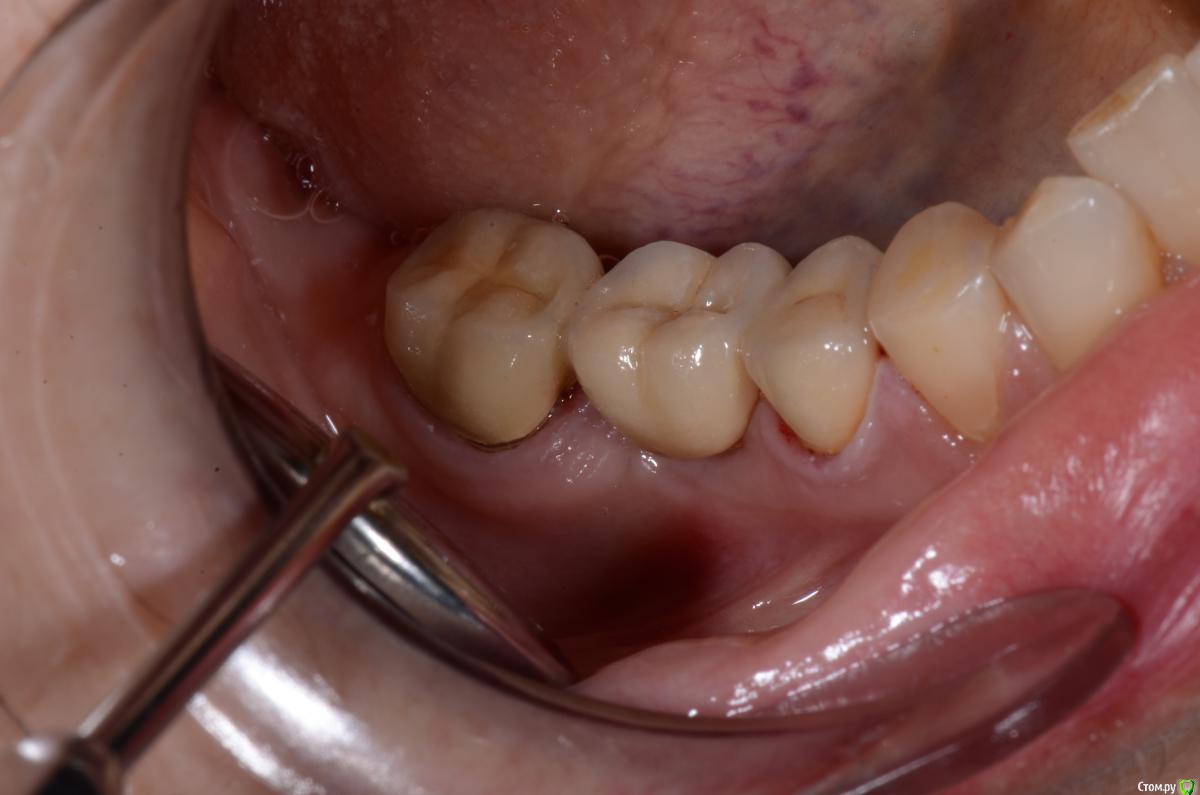

DimaKoleso Опубликовано 23 января, 2016 Поделиться Опубликовано 23 января, 2016 Решил выбросить на всеобщее обозрение вот такую работу. Ваше мнение? Делаете ли Вы гирлянду? В данном случае 47 зуб гирлянда 360, 45 зуб гирлянда 180 6 Ссылка на комментарий

DimaKoleso Опубликовано 24 января, 2016 Автор Поделиться Опубликовано 24 января, 2016 А где гирлянда?47 Ссылка на комментарий

DimaKoleso Опубликовано 24 января, 2016 Автор Поделиться Опубликовано 24 января, 2016 Да и не всегда эту гирлянду видео, если чуть-чуть уступ погрузить под десну, она эту гирлянду и прикроет. И будет всем щщщщастье) Ссылка на комментарий

Карен Аванесов Опубликовано 25 января, 2016 Поделиться Опубликовано 25 января, 2016 Широко для гирлянды. Техник хорошо постарался. Ссылка на комментарий

DimaKoleso Опубликовано 26 января, 2016 Автор Поделиться Опубликовано 26 января, 2016 Широко для гирлянды. Техник хорошо постарался.Да, мой косяк( Ссылка на комментарий